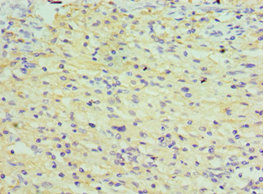

應用范圍:ELISA, IHC

Application Recommended Dilution IHC 1:20-1:200 -